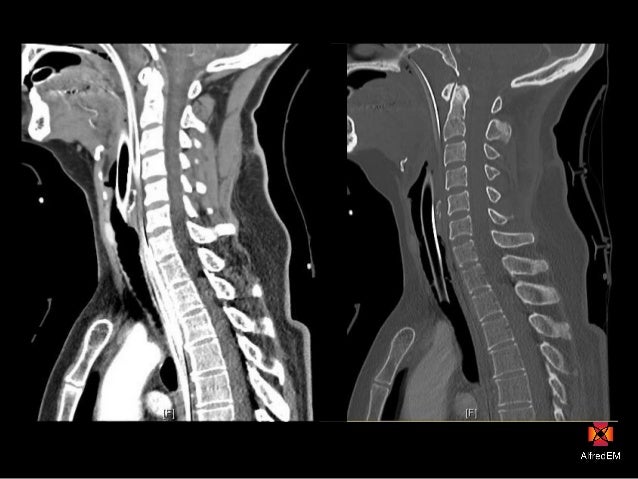

The spinal column is made up of many parts, all designed to help the back move flexibly, support body weight and protect the spinal cord and nerves.

Here the spine is concave, curving toward the belly (lordotic). This area is very flexible and a common location of injuries. Vertebrae can be grouped into four groups: a. Injuries to the bones, ligaments or joints The spine connects to the hip bones at the sacro-iliac joints via a complex arrangement of ligaments.Strain of the large muscles of the back that hold the spine upright.Irritation of the smaller nerves of the spine that involve innervate or supply the discs between the vertebrae, facets and ligaments.Irritation of the large nerves as they exit the bony confines of the spine leading to the arms and legs.While many of us take the benefits of a healthy spine for granted, spinal pain is a sharp reminder of how much we depend on our back in daily life. The spinal column combines strong bones, unique joints, flexible ligaments and tendons, large muscles and highly sensitive nerves. Five bones in the lower back-the lumbar spine.

12 bones in the chest-the thoracic spine.Seven bones in the neck-the cervical spine.The remaining small bones or ossicles below the sacrum are also fused together and called the tailbone or coccyx. The spine is divided into four regions which contain vertebrae: the cervical, the thoracic, the lumbar, and the sacral.Hover over each part to see what they do. Vertebrae are numbered and named according to where they are located in the spinal cord. It is made up of several vertebral bodies usually fused together as one. Interactive Parts of the Spine & Vertebrae Sections. The bottom of the spine is called the sacrum. Sometimes a person may have an additional vertebra, which is called a transitional body and is usually found at the sixth level of the lumbar area (labeled L6). These vertebrae protect the brain stem and the spinal cord, support the skull and allow for a wide range of head movement. By the time a person becomes an adult most have only 24 vertebrae because some vertebrae at the bottom end of the spine fuse together during normal growth and development. The average person is born with 33 individual bones (the vertebrae) that interact and connect with each other through flexible joints called facets. The spine is composed of 33 bones, called vertebrae, divided into five sections: the cervical, thoracic, and lumbar spine sections, and the sacrum and coccyx. The spine supports about half the weight of the body. Structural support for the body, allowing us to stand upright.

It provides several important functions, including: The human spine is a complex anatomic structure that is the scaffolding for the entire body.